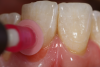

Fig 3. After using a very fine lead pencil to mark the curvilinear nature of the anatomical root area, a small spherical shaped amount of gingival colored composite material was placed on the tooth, light-cured, and used for shade determination with a custom shade tab.

Figure 3

Fig 4. Close-up view showing the pink composite shade estimation on the gingival tissue.

Figure 4